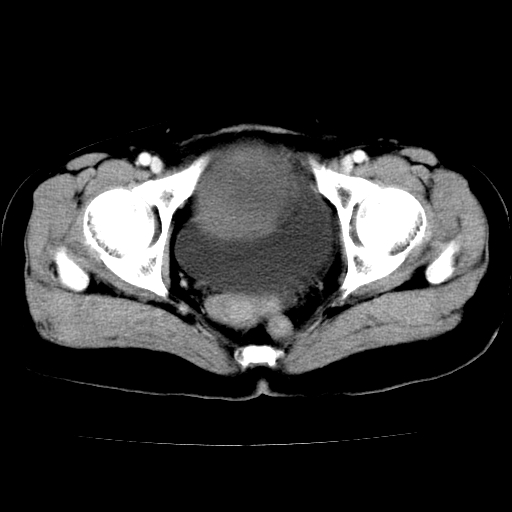

标题: CT24785:女,62岁,发现下腹部肿物半年。

女,62岁,发现下腹部肿物半年,下腹部不适。

老年女性患者,盆腔囊实性占位,ct增强不均匀强化,未见壁结节,未见腹水及盆腔积液,考虑附件囊腺瘤可能性大!

实性成分太多,要是囊腺瘤也要考虑恶性。